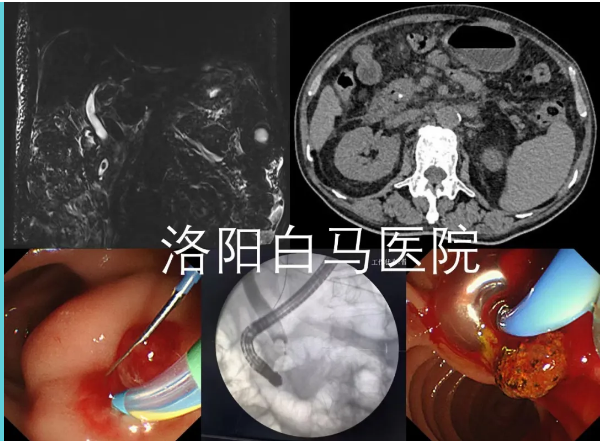

吕后宁主任首先为老人安排了上腹部CT检查。影像结果显示胆总管扩张,其末端可见高密度影,考虑结石可能。结合患者数年前曾有胆囊切除的病史,胆总管末端结石成为首要怀疑诊断。

为进一步明确结石的具体位置、大小,并排除其他可能引起梗阻性黄疸的病因(如胆管肿瘤、胆管狭窄等),随后为患者进行了MRCP检查。这项检查能更清晰地显示胆道系统的全貌。MRCP结果清晰证实了胆总管下端存在充盈缺损,即结石嵌顿,从而明确了胆总管末端结石”的诊断。这一严谨的步骤确保了诊断的准确性,为制定精准的治疗方案奠定了基础。

经全面检查评估,洛阳白马医院消化内科陈宏伟主任与吕后宁主任共同认为,采用经内镜逆行胰胆管造影(ERCP)取石术是适合该患者的优选方案。此项技术通过自然腔道(经口-胃-十二指肠)进行操作,体表无切口,具有创伤小、痛苦轻、恢复快的突出特点,对患者全身生理机能干扰较小,尤其有助于高龄患者平稳度过围手术期。

在充分的术前准备后,由陈宏伟主任与吕后宁主任共同为患者施行了ERCP取石术。术中,通过内镜精准定位,顺利将胆总管末端的结石取出,解除了胆道梗阻。